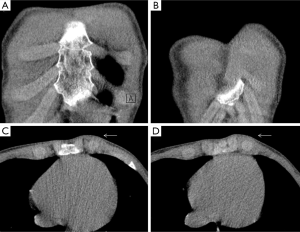

Injury to the rib-cartilage complex can occur at multiple sites along the anatomic arc from spine to sternum. Injuries to the chondrocostal junction (Figure 4) are termed rib separations, while nearby disruptions of the chondrosternal junction are called rib disruptions. The cartilage may itself be fractured (19). Radiographs, although useful for detecting osseous abnormalities, are insensitive to detect cartilage and soft-tissue abnormalities. Because costal cartilage injuries are often located in the junctional regions; chondrosternal and chondrocostal, the overlapping osseous structures in these areas limit the usefulness of radiographs. A Canadian study from Subhas et al. showed that cross-sectional techniques such as CT, US and MRI are more sensitive to detect these injuries (Figure 5) (20). On CT, cartilage density is relatively uniform (70–120 HU), in which this value is higher than fat and muscle but lower than calcium (Figure 6). Costal cartilage fractures are visualized as a low-density area through the costal cartilage, with surrounding calcifications near old fractures and gas density within the cleft in some cases. Swelling of surrounding soft tissue could also be seen. Other imaging techniques such as MDCT, US and MRI have been evaluated. In the largest published series, Malghem et al. described a series of eight patients with 15 costal cartilage injuries diagnosed on CT in all patients and on US in three of them. Their patient population was young (mean age, 27.5 years), and all of them had a prior traumatic injury, related to contact sports in three patients (19). Costal cartilage injuries are readily visible on MRI because of the high signal from the surrounding oedema; they are often more conspicuous than those of CT images. Even in cases of remote injury, high T2 signal was visualized at the site of fracture that was presumably due to non-union given the persistent clinical symptoms. In fact, the characteristically imaging appearance of MRI for cartilage injuries, as in ribs fractures, is an increase oedema-like signal on T2 at the site of injury. Also, oedema-like signal T2 could be seen in the surrounding soft tissue in recent or subacute injuries (<3 months). A fracture line, which is not always present, appears as a localized linear oedema-like decreased T1 and increased T2 signal, and it is best to be visualized on the fluid-sensitive sequences (fat-saturated fast spin-echo T2-weighted or STIR-weighted sequences) and in the coronal plane (20).

A rare clinical emergency so-called “deep tissue injury syndrome (DTI)” has been previously reported, characterized by a severe pressure ulcer necrotic tissue mass under intact skin (39). This unusual entity affects unconscious patients lying down in the same position after a long period of time, where thoracic wall muscles could be damaged. DTI can be identified using US (40), CT (41) and MRI (42). Soft-tissue swelling with myonecrosis is the hallmark of this pathology (Figures 15,16). It often requires surgical interventions and endangers the life of patients with motosensory impairments (43). Therefore, a delayed diagnosis must be avoided.